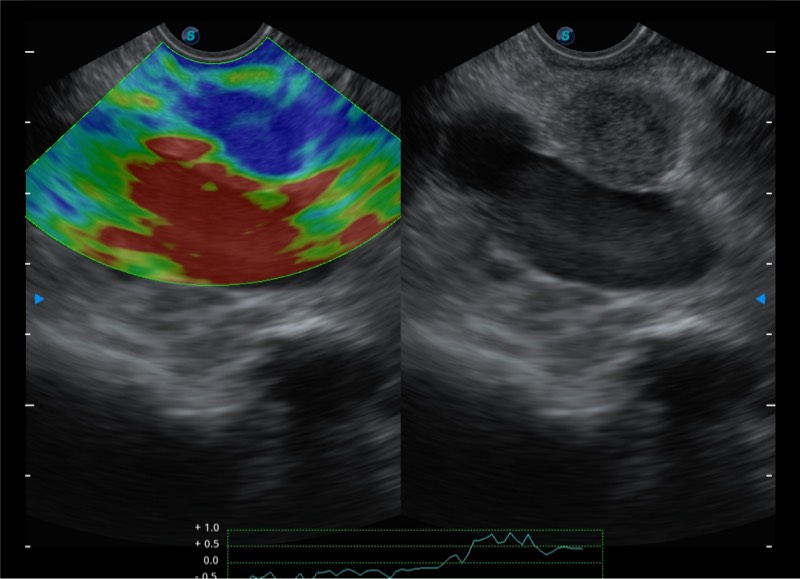

基于二十年的超声技术积累,乐玩lewin国际提供了最新一代的独立超声主机,在提供高质量图像的同时满足多学科使用。具备常见多普勒技术并提供弹性成像、声学造影等高端影像技术。新一代传感器具有更强的抗干扰能力并减少图像伪影。

150°超声扫描角度

4-12MHZ宽频输出